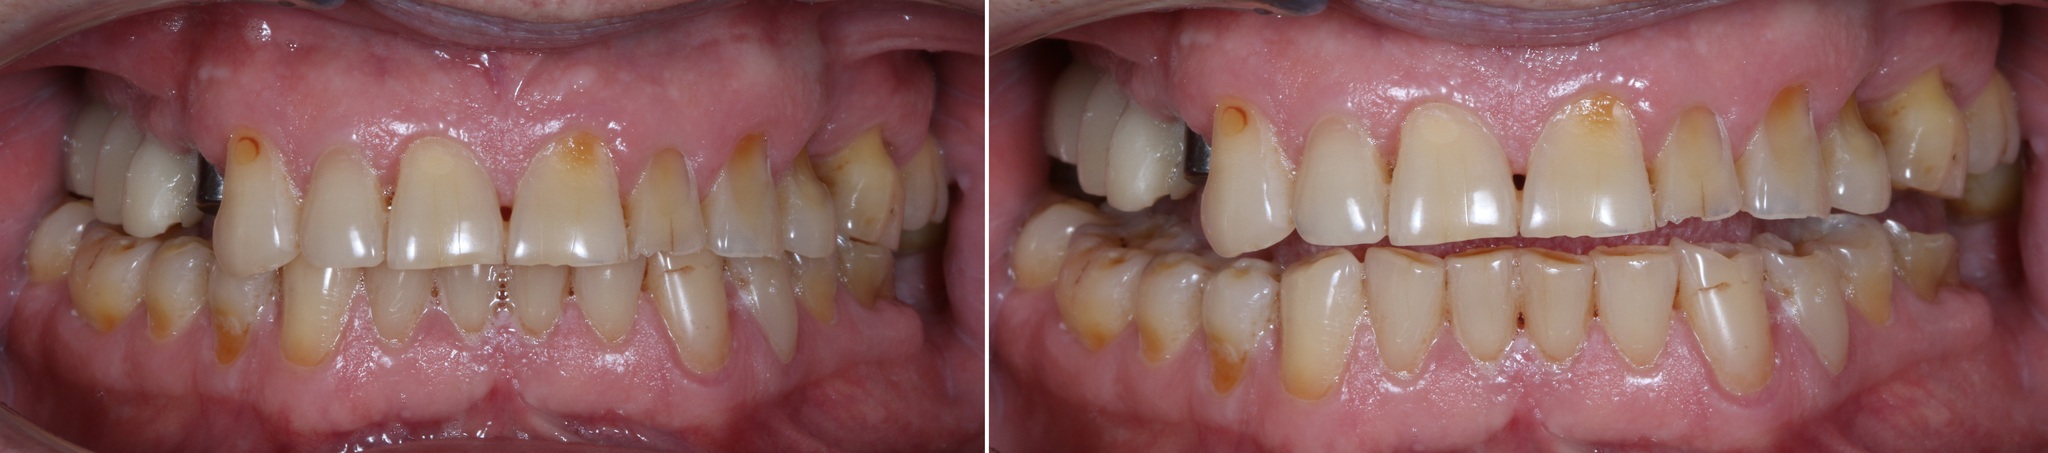

Обратите внимание, как сильно истерты зубы, а в области шеек этих зубов – клиновидные дефекты (некариозное поражение твердых тканей зубов, при которых зуб приобретает форму клина).

Основной причиной появления клиновидных дефектов является перегрузка из-за неправильного смыкания зубов.

Зубы за 3.5 года жизнь потрепала. Режущие края истерлись, появилось больше клиновидных дефектов:

Особенно не выдержал натиска времени 6й верхний левый зуб: